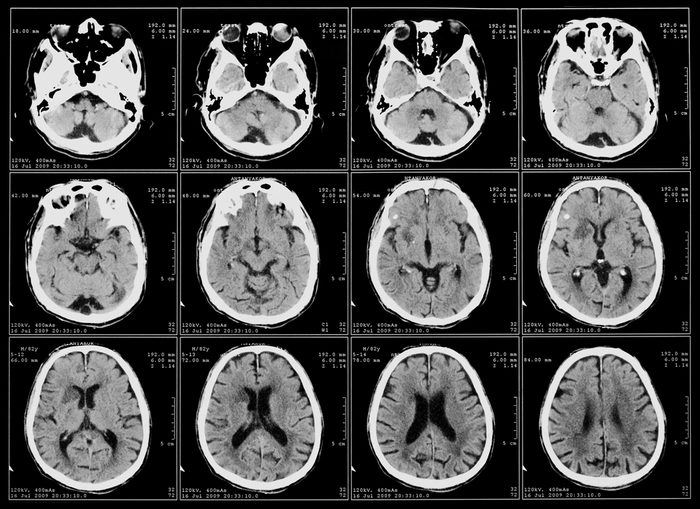

x-ray film of the brain computed tomography

khuruzero/Shutterstock

All of these chemical brain changes have a purpose

Not only do chemical changes in the brain make the experience more pleasurable, but they also have evolutionary value, according to Krellman. “Sex is vital to our survival as a species. So it makes sense that the act would be rewarding, pleasurable, and make us less vulnerable to physical discomfort that might interrupt the act,” he says.